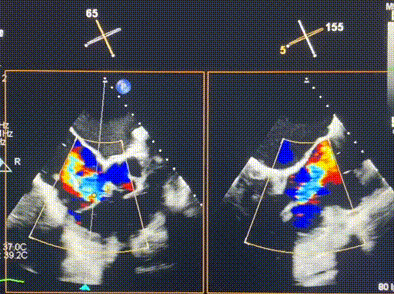

術(shù)前超聲提示重度三尖瓣反流

接受本次LuX-Valve Plus治療的是一位三尖瓣重度反流的高齡女性,患者早前曾由于二尖瓣疾病行經(jīng)導(dǎo)管二尖瓣置換術(shù),植入Tendyne瓣膜一枚,且有ICD植入史。術(shù)前CT分析結(jié)果顯示,瓣環(huán)大小為47.6mm,血管無明顯迂曲和鈣化。由于患者三尖瓣解剖結(jié)構(gòu)復(fù)雜,二尖瓣位人工瓣膜造成的超聲偽影和ICD導(dǎo)線的干擾使得歐洲沒有其他合適的商業(yè)化和臨床試驗的產(chǎn)品可以對其進行治療。經(jīng)過Rodrigo Estévez-Loureiro教授團隊的詳盡術(shù)前評估,認為LuX-Valve Plus經(jīng)導(dǎo)管三尖瓣置換系統(tǒng)可以對該患者進行有效的治療。因此,Rodrigo Estévez-Loureiro教授團隊最終決定使用這一中國創(chuàng)新器械為患者進行手術(shù)。法國波爾多里爾大學(xué)附屬醫(yī)院的Thomas Modine教授與加拿大圣保羅醫(yī)院的Anson Cheung教授全程線下指導(dǎo)本次手術(shù)。

手術(shù)在全麻狀態(tài)下進行。術(shù)者采用經(jīng)右側(cè)頸靜脈入路的方式將輸送器送入患者心臟內(nèi),在TEE及DSA引導(dǎo)下調(diào)整輸送器頭端角度,使得輸送器與三尖瓣瓣環(huán)平面垂直。在輸送器進入右心室后釋放室間隔錨定裝置,而后釋放瓣葉夾持件(2個耳片結(jié)構(gòu))成垂直狀態(tài)。在TEE及DSA確定夾持件固定至三尖瓣葉根部且位于右室側(cè)后釋放人工瓣心房側(cè)盤片。隨后調(diào)整瓣膜同軸性以及室間隔錨定件位置(貼合室間隔),前推藏針管并固定,進而釋放室間隔錨定裝置,并再次確認瓣膜位置、穩(wěn)定性及同軸性,合攏輸送鞘后撤出輸送器,完成LuX-Valve Plus人工三尖瓣瓣膜的植入,僅殘余微量瓣周漏。且經(jīng)手術(shù)中心電生理團隊評估,病人的起搏器和ICD功能沒有受到影響。

術(shù)后超聲顯示僅殘余微量瓣周漏

LuX-Valve Plus經(jīng)血管三尖瓣置換系統(tǒng)此次“出海”圓滿完成,術(shù)后Rodrigo Estévez-Loureiro教授對LuX-Valve Plus經(jīng)血管三尖瓣置換系統(tǒng)的器械性能和治療效果大為稱贊,認為LuX-Valve Plus的手術(shù)體驗非常好。術(shù)后即刻超聲顯示三尖瓣反流幾乎完全消失,血流動力學(xué)改善顯著,患者恢復(fù)快。在面對復(fù)雜解剖結(jié)構(gòu)、超聲影像質(zhì)量不佳、有起搏導(dǎo)線干擾時,Lux-Valve Plus也體現(xiàn)了極強的適應(yīng)性。Thomas Modine教授和Anson Cheung教授也肯定了LuX-Valve Plus術(shù)中操作的便捷性,認為LuX-Valve Plus容錯率高,對術(shù)中影像的依賴較小,后期希望可以更多的應(yīng)用LuX-Valve Plus三尖瓣置換系統(tǒng)于臨床實踐,讓更多的三尖瓣重度反流患者盡早獲益,改善預(yù)后。